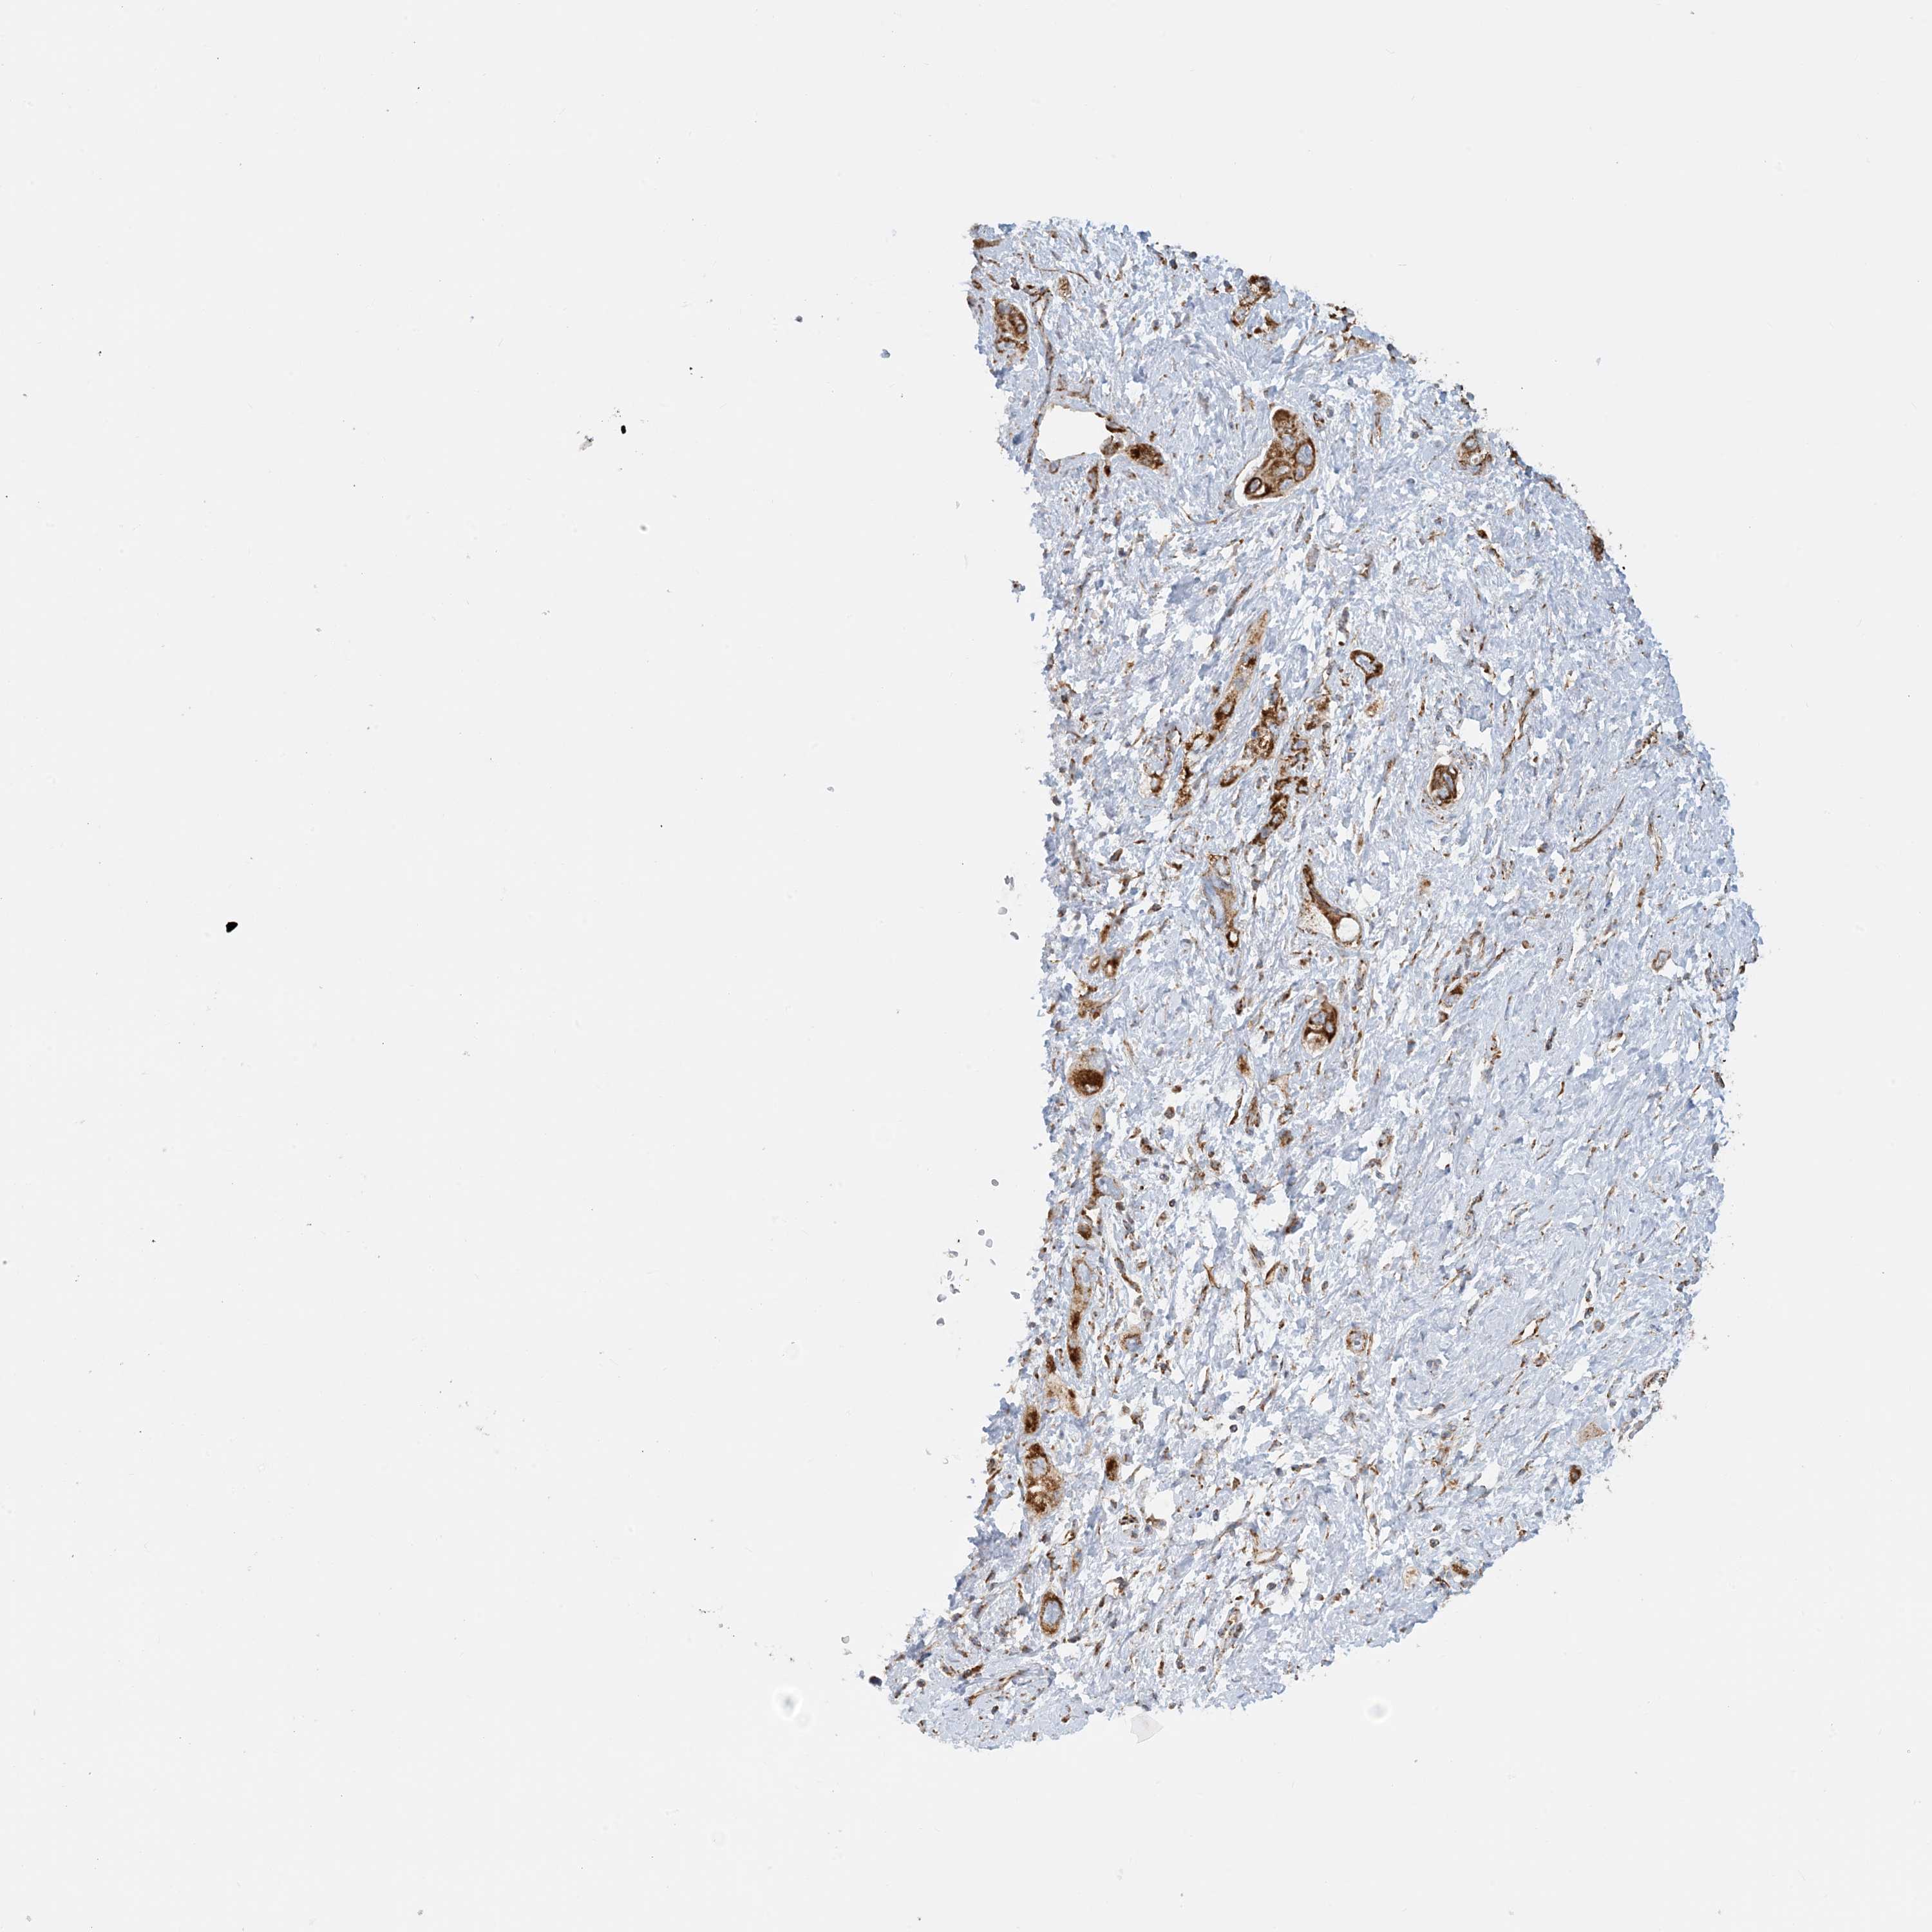

PANCREATIC CANCER - Protein expressioni

A mouse-over function shows sample information and annotation data. Click on an image to view it in a full screen mode. Samples can be filtered based on level of antibody staining by selecting one or several of the following categories: high, medium, low and not detected. The assay and annotation is described here.

Note that samples used for immunohistochemistry by the Human Protein Atlas do not correspond to samples in the TCGA dataset.

Antibody stainingi

Antibody staining in the annotated cell types in the current human tissue is reported as not detected, low, medium, or high, based on conventional immunohistochemistry profiling in selected tissues. This score is based on the combination of the staining intensity and fraction of stained cells.

Each image is clickable and will lead to virtual microscopy that enables deeper exploration of all samples and also displays staining intensity scores, fraction scores and subcellular localization as well as patient and tissue information for each sample.

Antibody HPA031966

Staining

High

Medium

Low

Not detected

Intensity

Strong

Moderate

Weak

Negative

Quantity

>75%

75%-25%

<25%

None

Location

Nuclear

Cytoplasmic/membranous

Cytoplasmic/membranous,nuclear

Adenocarcinoma, NOS